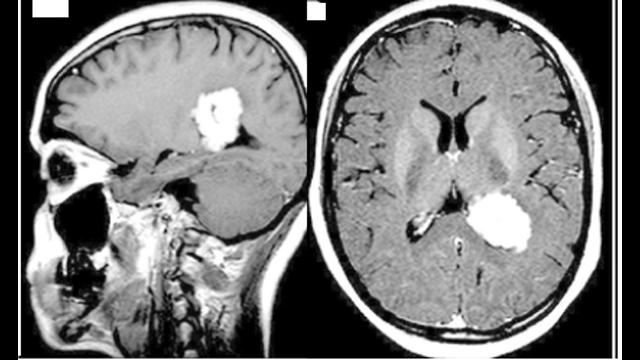

78 year old male with metastatic myeloma presenting with AMS , polyuria and neutropenic fever.